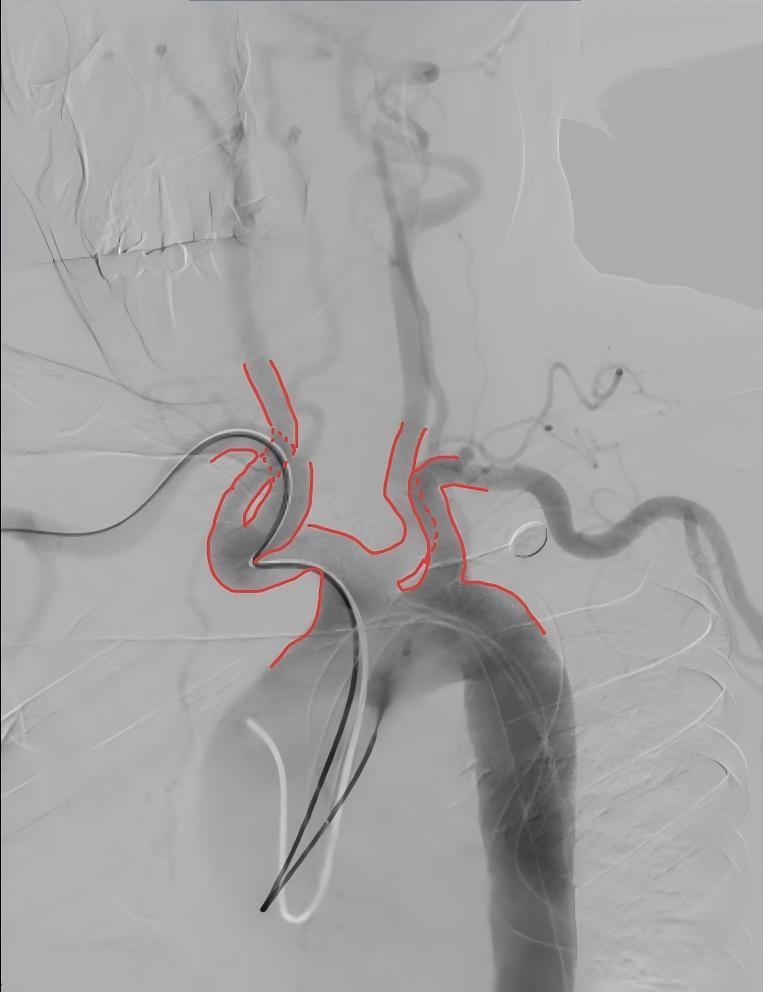

一场与死神赛跑的救治随即展开,但困难也接踵而至。急诊脑血管造影检查揭示了更严峻的情况——患者主动脉弓呈现“牛角弓”形态,这种解剖变异使得传统经股动脉入路的导管难以顺利到达颅内血管,不仅延长手术时间,还可能增加血管损伤风险。

何为“牛角弓”形态?李继树介绍,这是主动脉弓上血管头臂干和左侧颈总动脉共同起源与左侧锁骨下动脉拼凑形似“牛角”。一般来说,正常主动脉弓像张开的弓,血管开口角度平缓,而“牛角弓”患者的血管开口几乎垂直向上,导管进入脑血管如同“反向急弯+爬陡坡”。

基于神经介入手术团队积累的经桡动脉穿刺操作经验,在征得患者家属同意后,神经内科主任唐记协调导管室、麻醉科、ICU快速完成术前准备,启动经桡动脉介入治疗预案。在局部麻醉下,医生于患者右手腕部桡动脉穿刺,通过直径仅2毫米的导管,在DSA影像引导下小心翼翼穿过扭曲的血管迷宫,克服“牛角弓”解剖难点,顺利完成脑血管造影,发现此次发病根源——左侧大脑中动脉M1分叉部动脉瘤。手术团队仅用15分钟便成功将微导管送达颅内动脉瘤部位。

随后,通过微导管精准植入数枚弹簧圈,逐步闭塞动脉瘤腔。整个手术历时89分钟,比预计时间缩短近一半。术后造影显示动脉瘤完全栓塞,载瘤动脉通畅,患者麻醉清醒后意识状态明显改善。